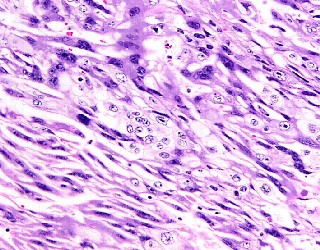

組織学的には,紡錘形細胞の不規則な束状配列と多角形の細胞の充実性胞巣状配列が

混在しており,著明な出血,壊死を伴っていた(画像2,3).紡錘形細胞はクロマチン

が増量した異型核と両染性の胞体をもち,細胞境界は不明瞭であった.一方で,多角形の

細胞は核小体明瞭な異型核と淡明な胞体をもち,細胞境界は明瞭であった.腺腔形成や

乳頭状構造,あるいは粘液産生などの腺癌を示唆する所見はみられず,また,扁平上皮癌を

示唆する所見は認められなかった.以上の所見から,本腫瘍は絨毛癌が最も疑われたが,

間葉系悪性腫瘍や悪性上皮性・間葉系混合腫瘍の可能性も除外できなかった.免疫組織化学

的に,腫瘍細胞は,human chorionic gonadotropin(画像4),human placental lactogen,

human placental alkaline phosphatase,およびCAM5.2に陽性で, vimentin,a-SMA,

desmin,S-100には陰性であった.